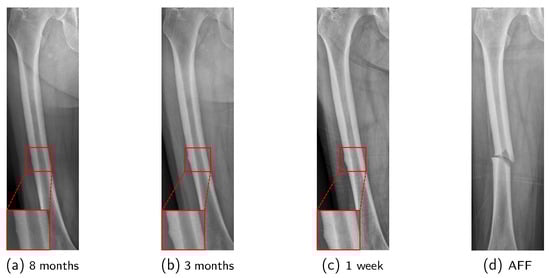

In the early stages preceding the occurrence of AFF, cortical buckling will develop in the lateral cortex of the femur due to repeated cycles of microfracture and healing [12]. This condition is termed Incomplete Atypical Femoral Fracture (IAFF). IAFF exhibits various characteristics and is classified based on its location as shown in Figure 1: Diaphyseal IAFF (D-IAFF), which occurs in the femoral shaft, and Subtrochanteric IAFF (S-IAFF), which occurs in the subtrochanteric region [13]. Although IAFF is a crucial precursor to AFF, it is often asymptomatic or presents with vague features, making detection difficult and often resulting in delayed diagnosis. As a precursor to AFF, the progression process from IAFF to AFF is illustrated in Figure 2. IAFF is typically diagnosed through bone scans [14] or Magnetic Resonance Imaging (MRI) [15]. However, these diagnostic methods have notable drawbacks, including high costs and time consumption. Furthermore, there remains the risk of misdiagnosis [14], which can lead to either unnecessary or delayed interventions, ultimately culminating in a complete fracture.

To mitigate these problems, the development of a diagnostic support system utilizing X-rays is essential, but there are several obstacles to be overcome: (1) An IAFF is often extremely small in size, (2) lacks distinct characteristics, and (3) is similar to normal anatomical deformations, making it easy to overlook. Additionally, (4) the location and features of an IAFF vary depending on the type, and (5) its appearance may differ slightly depending on the radiographic view, even for the same patient (Figure 3). Due to these factors, even experienced orthopedic specialists may miss an IAFF if they do not examine it meticulously.